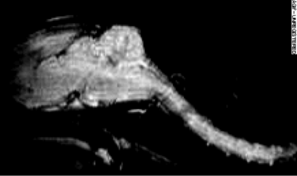

アカゲザル(n=2)のグループ解析 - ラットのresting state fMRI

Oxytocin 投与前後の functional connectivity(oculomotor network の cross correlation)